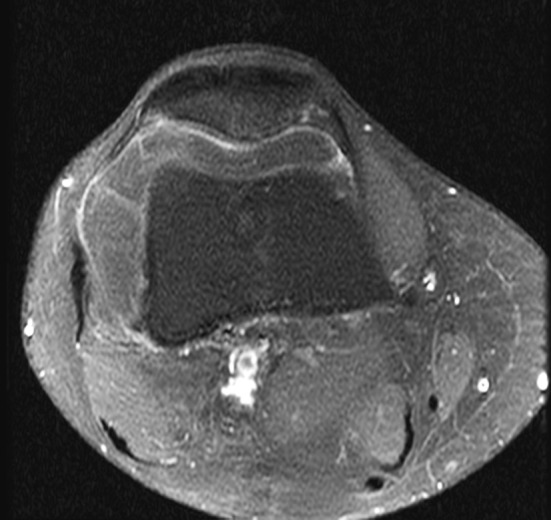

Fig. 2A–D.

(A) Axial T1-weighted, (B) coronal T-1 weighted, and (C) axial T2-weighted MR images show the large soft tissue mass in the suprapatellar pouch having the same signal intensity as the subcutaneous fat and a thin fibrous internal septum with low signal intensity on T1- and T2-weighted images. (D) On an axial proton density fat saturation MR image, the lesion appears hypointense and has the same signal intensity as the subcutaneous fat. Minimal joint effusion outlining the capsule was observed.

Fig. 3.

An axial T1-weighted MR image shows mild peripheral enhancement of the soft tissue mass after intravenous administration of gadolinium contrast.

AP (Fig. 1A) and lateral (Fig. 1B) radiographs of the right knee showed a radiolucent soft tissue mass in the anterolateral aspect of the knee. There was no visible bone destruction or other lesion identified. MRI revealed one large soft tissue mass in the suprapatellar pouch that had the same signal intensity as the subcutaneous fat and an internal septum with low signal intensity on T1- and T2-weighted sequences within it (Fig. 2A–C). Minimal joint effusion outlining the joint capsule also was seen on an axial proton density fat saturation image (Fig. 2D). The soft tissue lesion also showed mild peripheral enhancement pattern on postgadolinium T1-weighted MRI (Fig. 3).

Typically, MRI findings of an intraarticular lipoma are high signal intensity on T1- and T2-weighted images that is isointense relative to subcutaneous fat tissue and contains thin delicate thin fibrous septa.